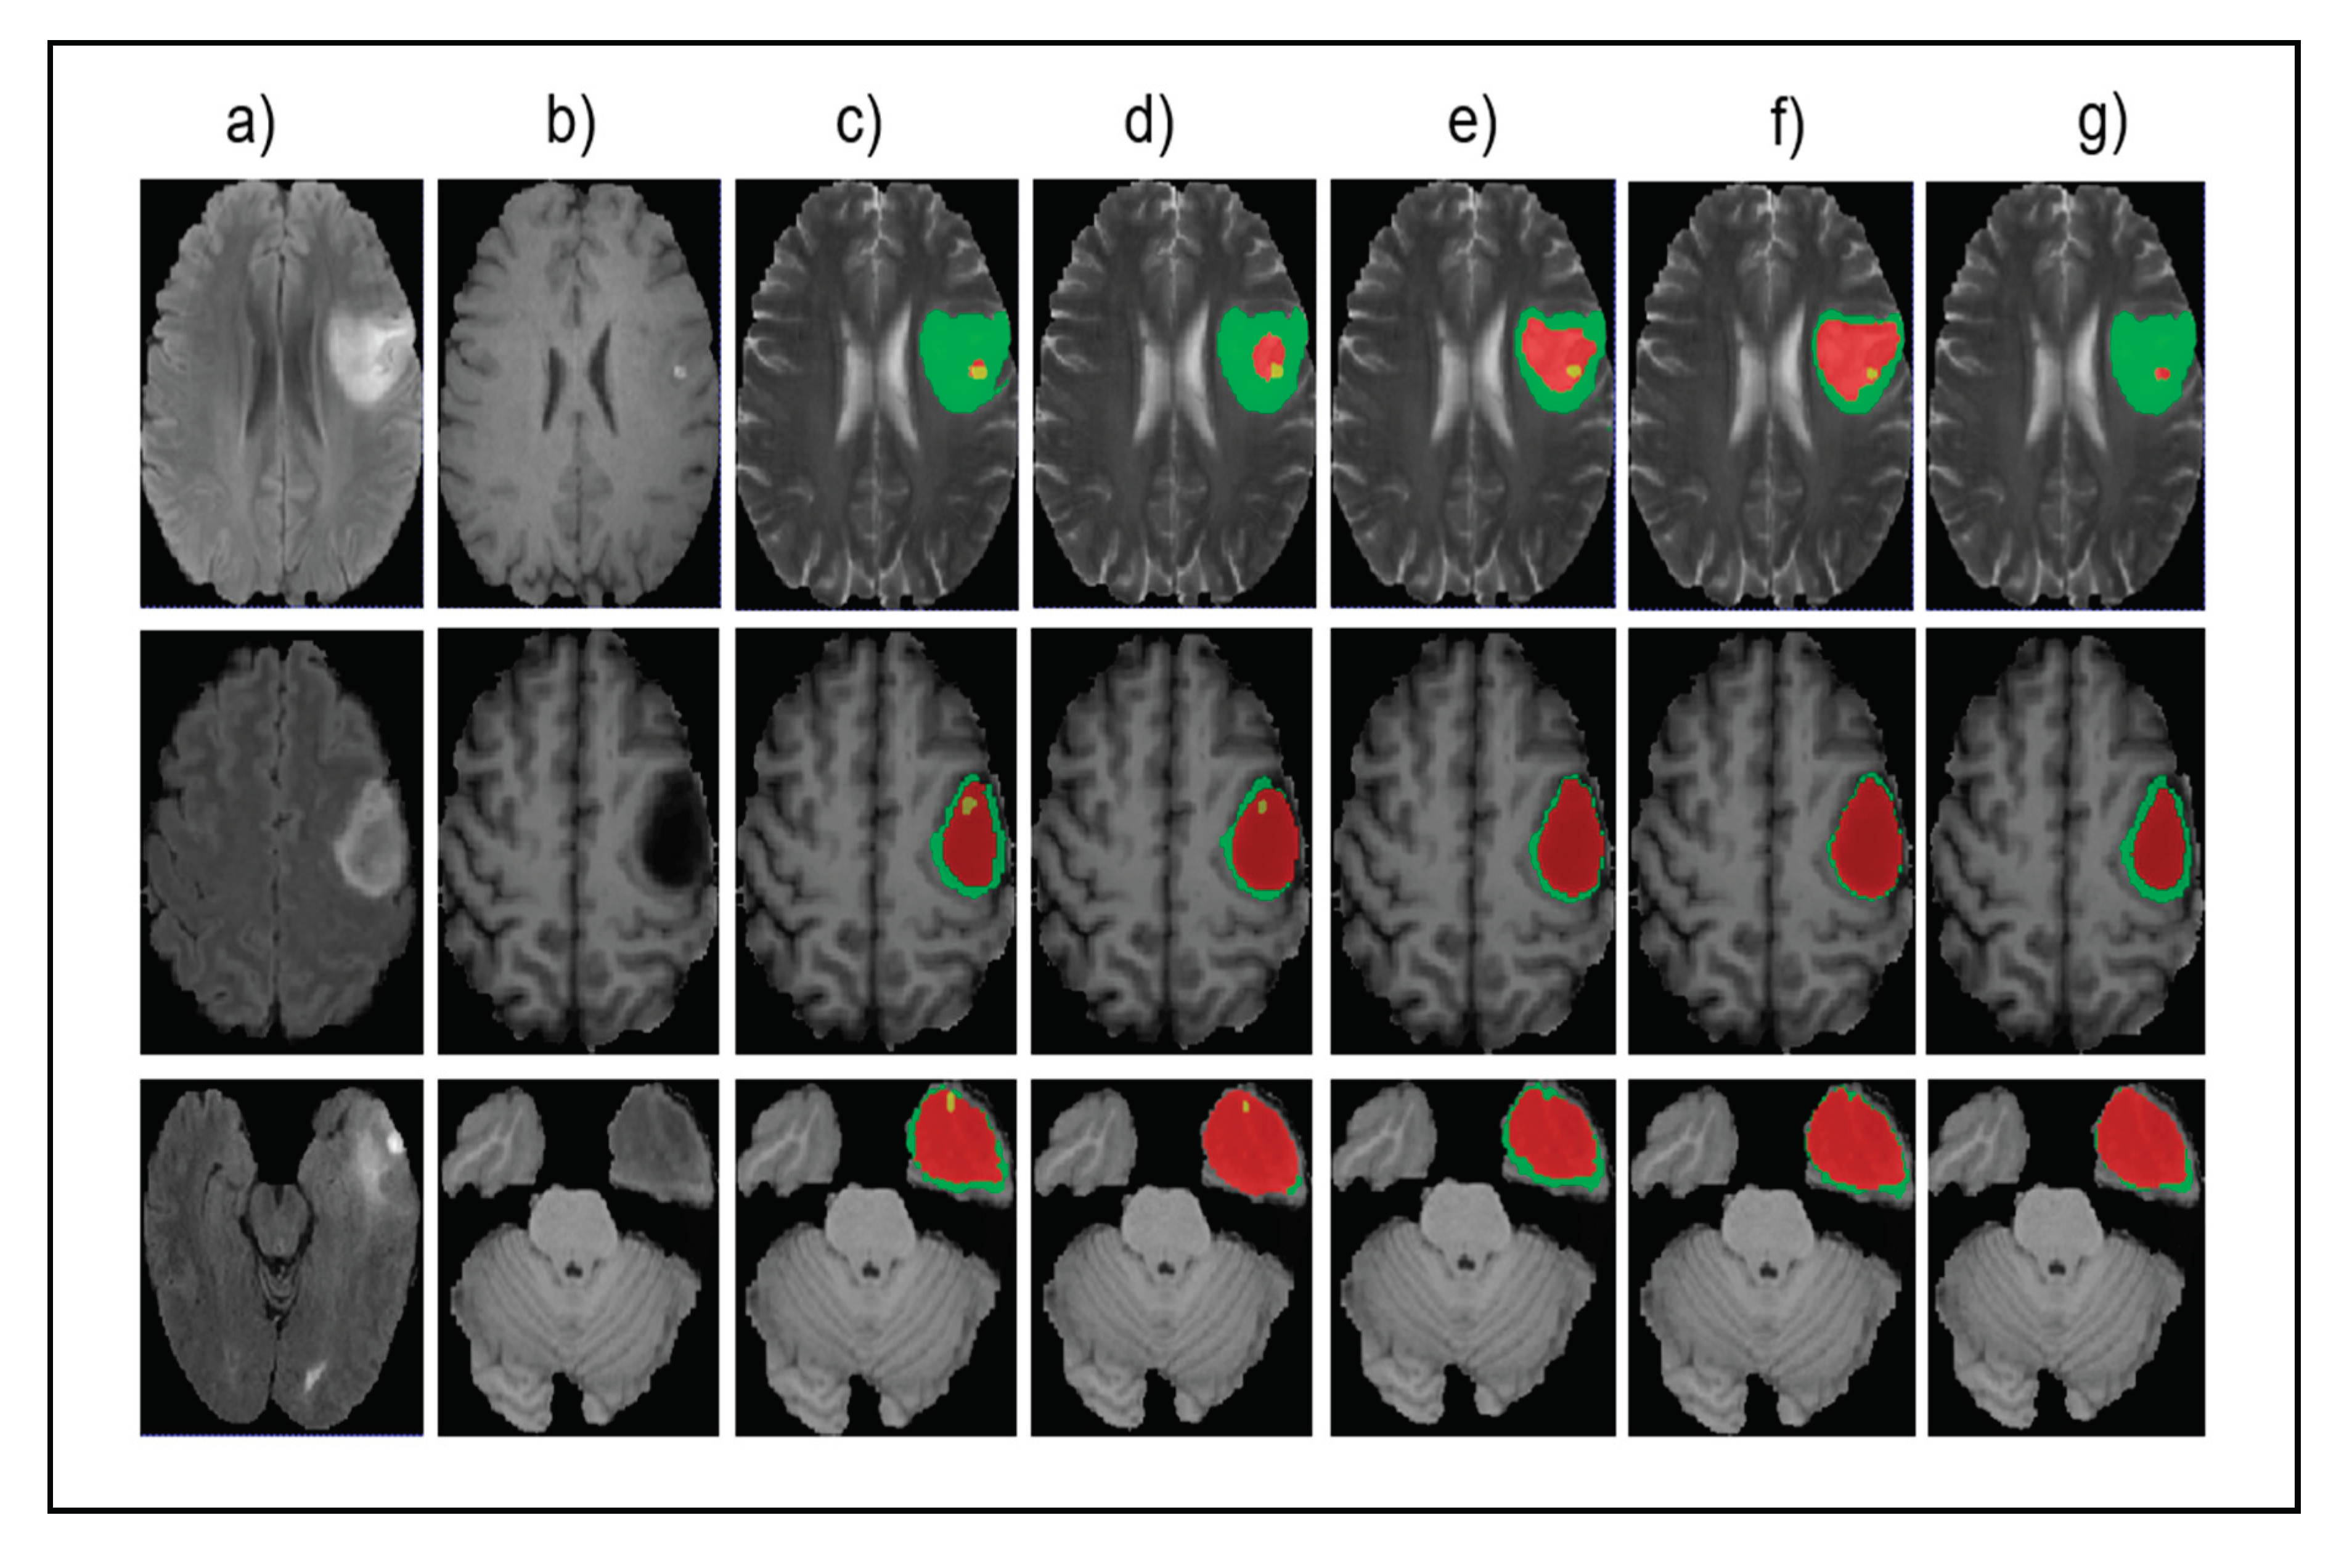

Figure 5 shows the input images, ground truth, and segmentation results of the enhancing tumor predicted by four models including our model, ReversibleUnet [48], No New-Net [49], and DMFNet [43]. As shown in the first row of the figure, ReversibleUnet and No New-Net predicted high false negatives on the enhancing tumor (yellow color), DMFNet failed to segment the enhancing tumor area while our model can accurately segment them. In the second and third rows of Figure 5, we can see that our model could segment the area of small enhancing tumor while other models failed to segment them. Figure 6 shows the dice similarity coefficient (DSC) stratified by tumor size.

Figure 5.

Qualitative comparison of different models for small tumor segmentation. (a) Input fluid attenuated inversion recovery (FLAIR) image. (b) Input T1 image and (c) ground truth images. (d) Results of our method. (e) Results of ReversibleUnet [48]. (f) Results of No New-Net [49]. (g) Results of DMFNet [43].